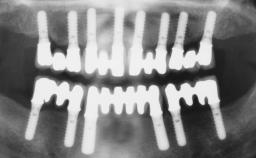

Immediate Loading of Four Implants in the Mandible and Final Restoration with a Full-Arch Metal Framework FDP

Pedro Tortamano, Luiz Otávio Alves Camargo

A fully edentulous 65-year-old woman was referred to our clinic for esthetic and functional dental rehabilitation. The patient presented with inadequate complete maxillary and mandibular prostheses, insufficient vertical dimension, and extensive tooth wear. The clinical examination and anamnesis showed no local or systemic contraindications, no signs or symptoms of bruxism, and an absence of smoking habits. The treatment proposed was implant placement in the mandibular interforaminal area and immediate loading with a fixed definitive prosthesis. A removable mucosa-supported complete prosthesis was indicated for the upper jaw, since its bone structure offered satisfactory retention and the financial condition of the patient disfavored a full-mouth implant-supported rehabilitation.

# of Implants 4

Type of Implants One-Piece

Prosthesis Type FDP

Loading Protocol Immediate